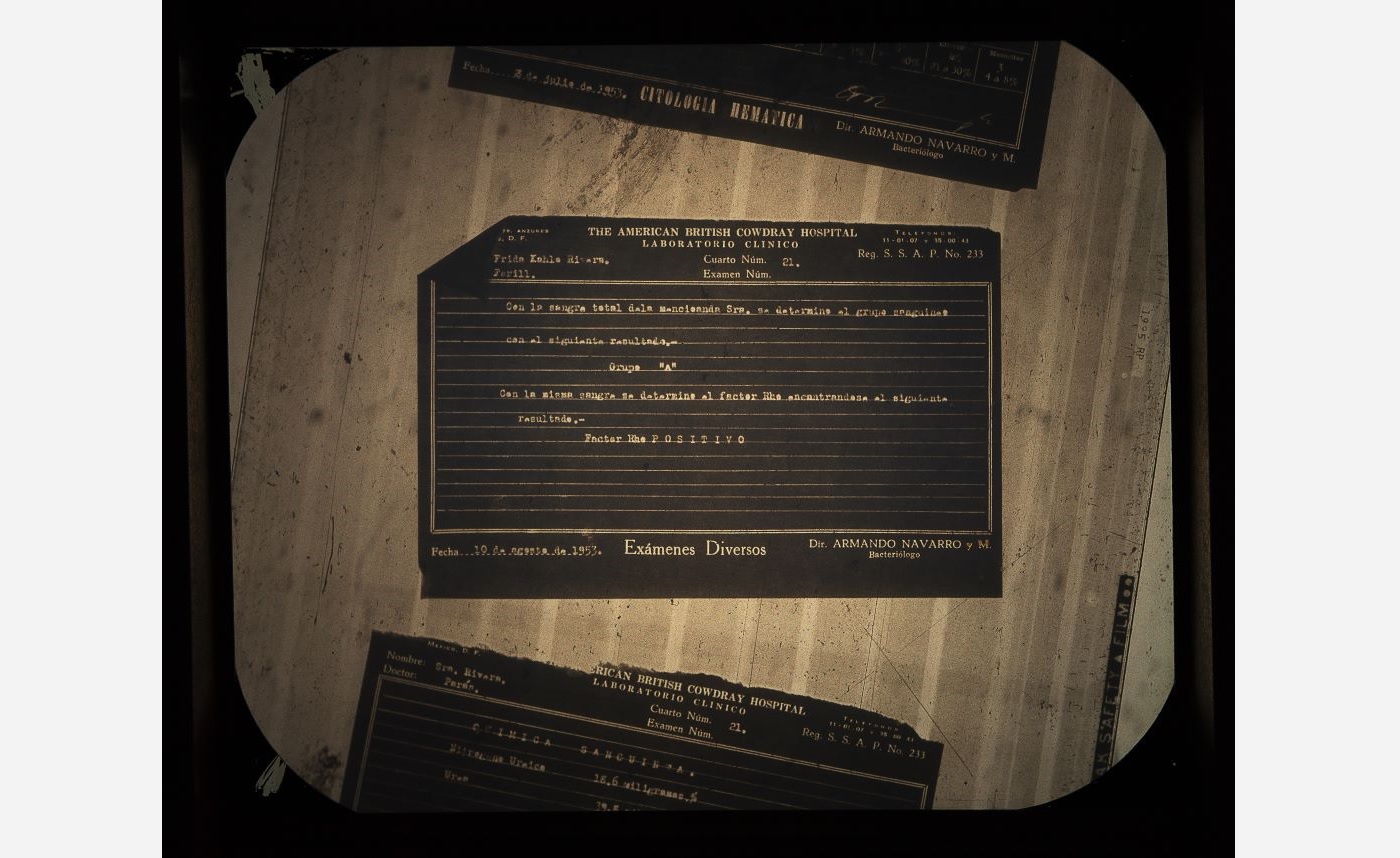

At the age of 6, Frida Kahlo contracted polio virus, resulting in her right leg being shorter and thinner. This physical disability was further complicated by the streetcar accident, in 1925, that caused 11 fractures in her right foot. As a result, Frida lived with chronic pain in her lower limbs, often having to be treated for foot ulcers that were largely due to vascular insufficiency. Eventually doctors amputated five phalanges, or bones in Frida’s right foot as well as a smaller bone, the sesamoid.

The last major recorded surgery Frida Kahlo underwent was an amputation of her right leg, on 11 August 1953—less than a year before her passing. The amputation was performed due to Frida having been diagnosed with gangrene—a medical condition that involves the death of body tissue due to a lack of blood flow or a serious bacterial infection.

Cristina Kahlo Alcalá, American British Cowdray Hospital File (Clinical Sheet), 1953, 2023, lightbox installation, Courtesy of the artist and Centro Médico ABC Historical Archive. © Cristina Kahlo

Cristina Kahlo Alcalá, American British Cowdray Hospital File (Clinical Sheet), 1953, 2023, lightbox installation, Courtesy of the artist and Centro Médico ABC Historical Archive. © Cristina Kahlo -

Cristina Kahlo Alcalá, American British Cowdray Hospital File (Clinical Sheet), 1953, 2023, lightbox installation, Courtesy of the artist and Centro Médico ABC Historical Archive. © Cristina Kahlo

Cristina Kahlo Alcalá, American British Cowdray Hospital File (Clinical Sheet), 1953, 2023, lightbox installation, Courtesy of the artist and Centro Médico ABC Historical Archive. © Cristina Kahlo

The ABC hospital was where Frida stayed for almost a year in 1950—undergoing seven spinal surgeries—and where in 1953 her lower right limb was amputated under the care of Dr. Juan Farill. Frida was treated at the ABC hospital until her passing in 1954.